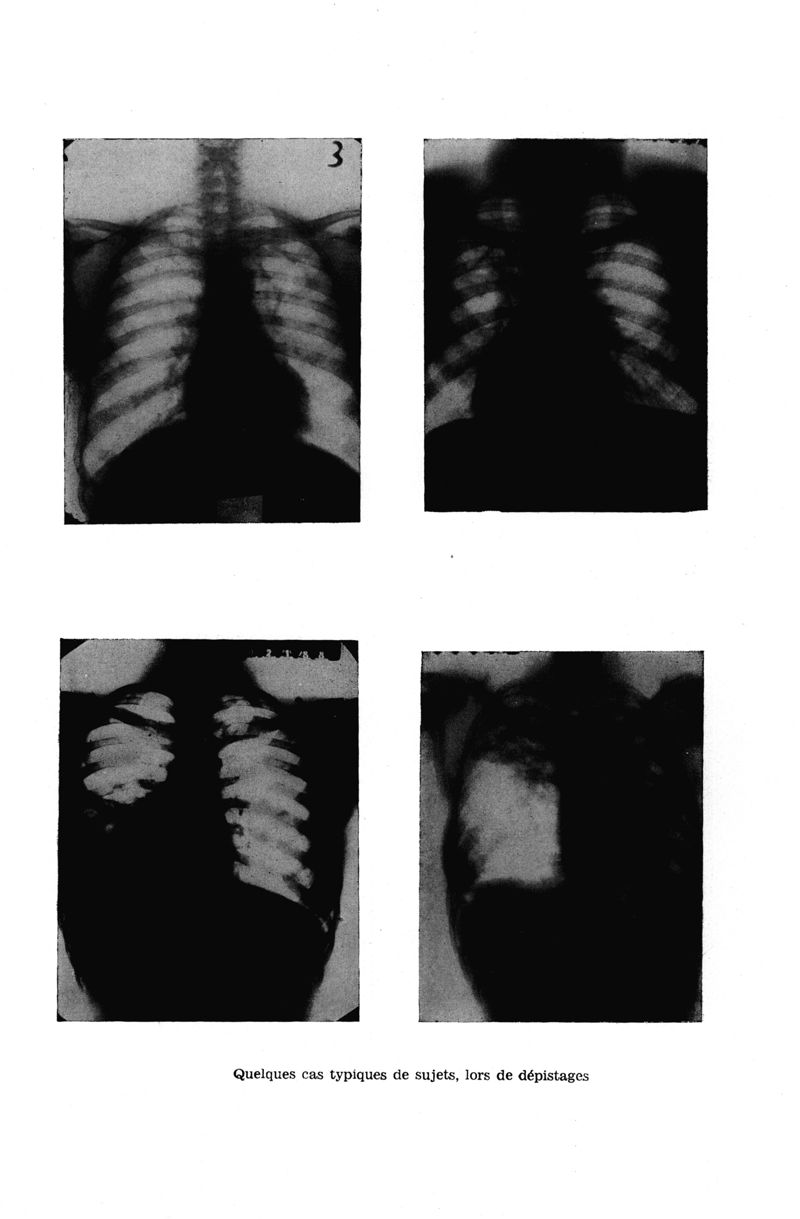

Médecine tropicale : Revue du corps de santé colonial

. - Marseille : Ecole d'application du service de santé des troupes coloniales, 1956.